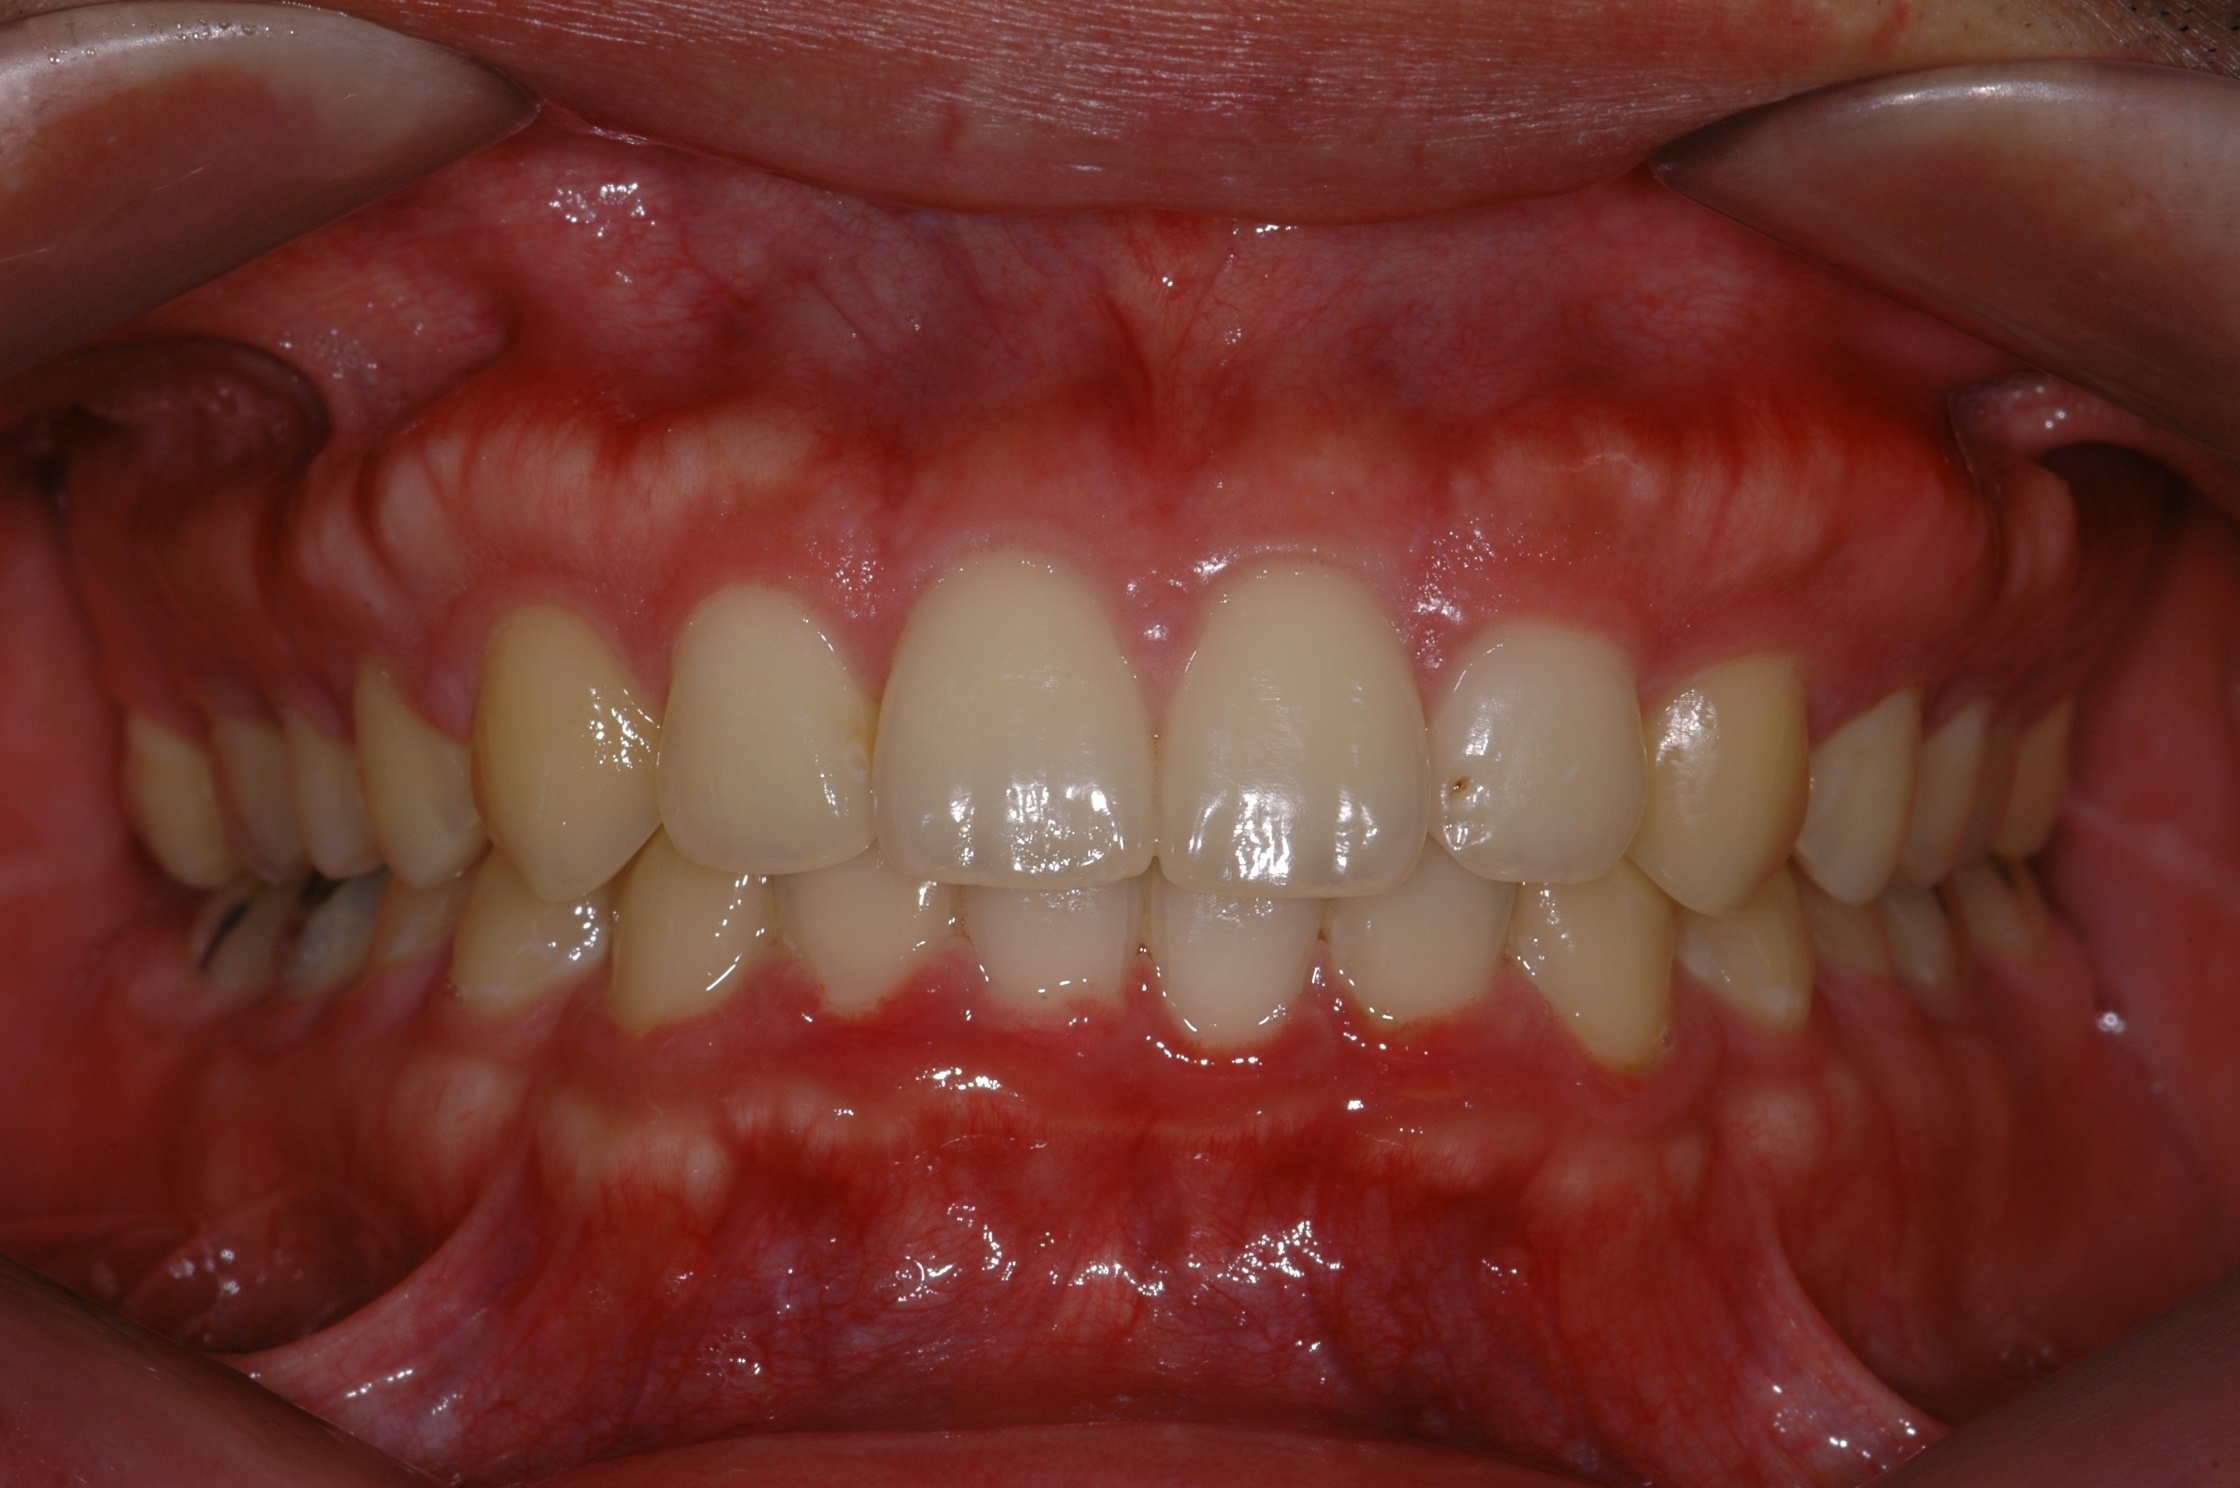

치료 전 사진입니다.